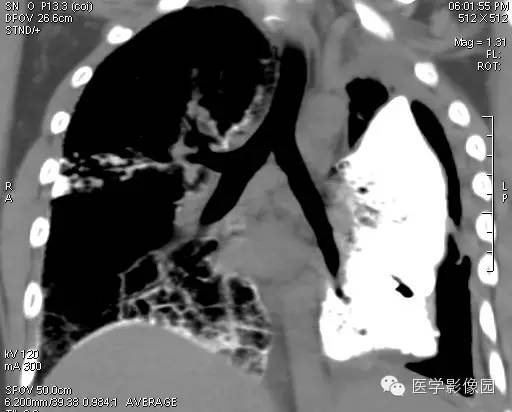

【病例】尘肺1例X线及CT影像表现

男性,36岁,镀锌工作史1年。

尘肺的主要病理改变为肺间质弥漫性纤维化及弥漫性灶周肺气肿,主要累及周围肺组织和支架结构,如肺泡壁、小叶间隔和支气管血管周围组织。

小结节影:多为双肺弥漫性或散在小结节影,表现为类圆形影,边界清晰,以中下肺为主,背侧多见。

大阴影:多为块状大阴影,表现为不规则卵圆形影,边缘凹凸不平,多有粗大索条影,伴疤痕性肺气肿,其内可见点状、斑片状钙化,坏死或空洞。

胸膜改变:可见胸膜肥厚、粘连及钙化缘怨例。

肺门改变: 肺门影增大,肺门多伴点状或蛋壳状钙化。

肺纹理:扭曲及变形改变。